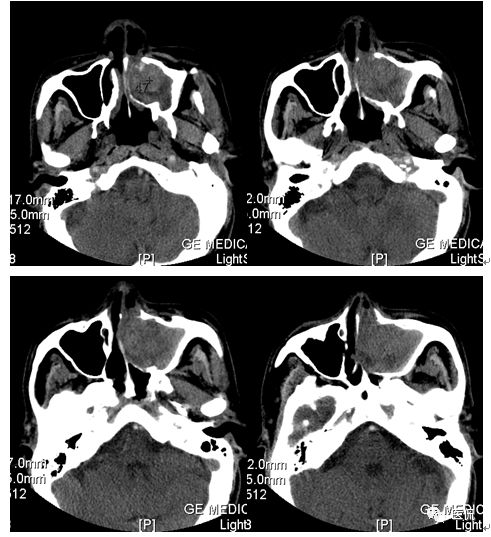

增强水平位FST1WI

CT平扫及增强示:左侧上颌窦及鼻腔可见软组织密度影,呈膨胀性生长,周围骨质压迫性吸收破坏,累及左眶,病灶密度不均匀,周边区可见点状钙化,增动脉期轻度强化,局部见小灶性稍高密度区,静脉期病灶内见不均匀明显强化,CT值最高达117HU,延迟期强化范围有所增大。

本例病灶较大,周围骨质可见吸收破坏,并累及眼眶,病灶内少量钙化,增强扫描具有一定特征性,表现为动脉期轻度强化,局部见小灶性稍高密度区,静脉期病灶局部呈明显强化,CT值最高达117HU,延迟期强化范围有所增大,呈延迟渐进性强化的特点,推测为病灶内出血所致。